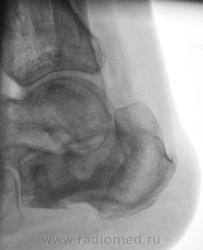

Лечение состояло из "множества рентгенов" и гипса. Срок - 5 месяцев.

Сейчас думают об остеомиелите.

Контуры пяточной кости относительно четкие, разрежение структуры пяточного бугра, в проекции перелома уплотнение структуры кости( имею в виду последние снимки).Клиника остеомиелита есть?

Во-первых, деформация пяточной кости; во-вторых, отсутствие консолидации, через некоторое время и ложный сустав сформируется. Неоднородное уплотнение костной структуры в теле кости может быть обусловдено как остеомиелитом, так и перераспределением нагрузки.

Признаков остеомиелита не вижу, только консолидир перелом с неуд стоянием отломков.